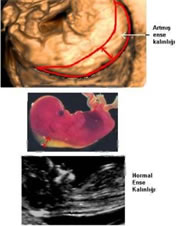

Fetal ense kalınlığı, ultrasonografide bebeğin boynunun arka kısmında koyu renkli olarak görünen kısmı anlatmak için kullanılan bir terimdir. Terimin ingilizcedeki orijinal şekli "nuchal translucency"dir. Gebelik ilerleyip bebek büyüdükçe ense kalınlığı da giderek artar. Bu nedenle ölçüm 11-14. haftalar arasında yapılabilir ve büyük dikkat gerektirir. Ölçüm yapılırken yapılacak milimetrik bir hata risk oranlarında büyük değişikliğe neden olabilir

Yapılan çok sayıda araştırmada 11 ile 14. gebelik haftaları arasındaki fetal ense kalınlığı ile Down sendromu başta olmak üzere bazı kromozom anomalileri arasında sıkı bir ilişki olduğu ortaya konmuştur.

Nicholaides ve arkadaşlarının artmış ense pilisi kalınlığının ne ölçüde değerli olduğunu araştırdıkları bir çalışmada 3 mm lik NT ölçümü ......3 kez artmış risk 4 mm lik NT ölçümü.......18 kez artmış risk 5 mm lik NT ölçümü.......28 kez artmış risk göstergesi olarak kabul edilmiştir. Örneğin 35 yaşında her kadın için Down sendromu riski 1/270 dir.Eğer NT ölçümü 4 mm ise 1/270 olan risk 18 kat artarak 1/15 e çıkacaktır.

Ense kalınlığı ölçümü kan değerleri, ile beraber bakıldığı vakit testin duyarlılığı %90’ı bulur.